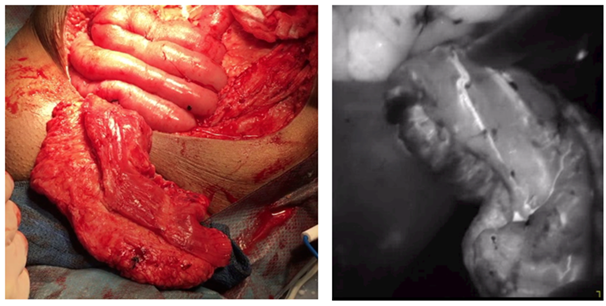

In addition, the stoma site itself can be subject to complications such as stomal stenosis related to undue tension on the conduit pedicle as the stoma is brought through the skin, leading to pressure on the vasculature. Typically, a pink appearance is considered acceptable for the stomal opening and is generally deemed sufficient to indicate healthy tissue, however, ICG provides the potential to confirm viability (Figure 6). While no current reports exist on this aspect, theoretically ICG utilization to assess stomal vascularization could have a contributing hand to decrease need for stomal revisions.12 Lastly, in certain complex cases of aggressive resection for pelvic disease, vascularized flaps may be required to provide tissue coverage for large defects in the pelvis or perineum. Lack of adequate tissue for primary closure or prior radiation provides challenges to the operating team. To prevent poor or non-healing wounds and provide adequate support which can be obtained via plastic surgery placement of local or distant flaps with or without skin like the vertical rectus abdominis muscle flap (VRAM) or free flaps like the latissimus dorsi flap.13 In these cases, identifying and incorporating well-perfused flaps are crucial to ensure optimal post-operative outcome. As appreciated in Figure 7, ICG can also be implemented to assess perfusion and viability of the flap prior to closure. Thus, there are multiple opportunities during complex pelvic extirpative procedures including radical cystectomy for ICG to assess tissue perfusion and reduce tissue and patient complications.

Figure 7 Fluorescent imaging depicting adequate vascularity and blood flow to the vertical rectus abdominis muscle (VRAM) flap to be utilized for wound coverage during pelvic exenteration. White light imaging appreciated on the left.